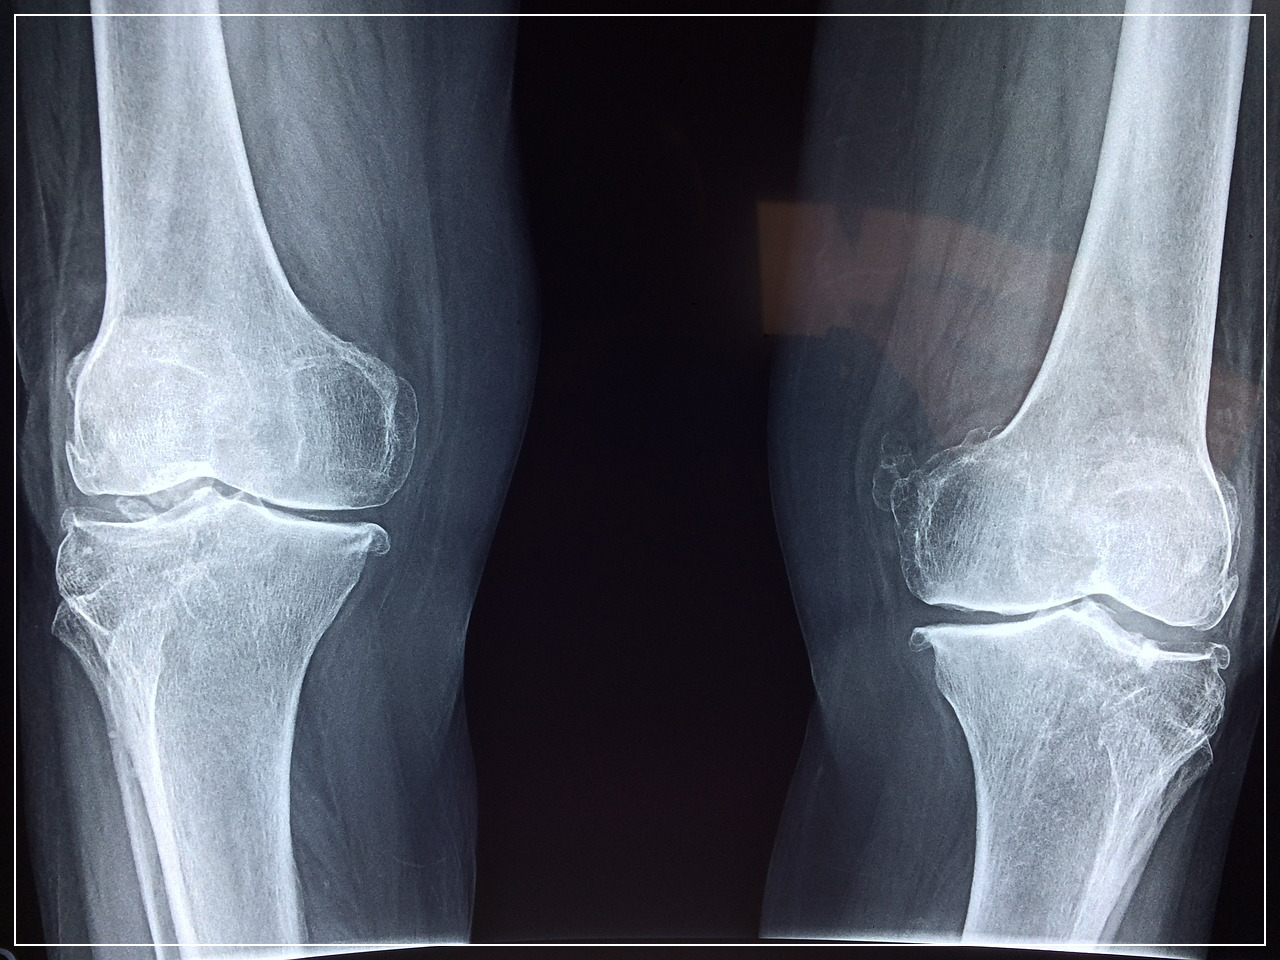

1. 무릎 통증의 주요 원인 질환 3가지

- 퇴행성관절염: 연골이 닳아 통증. 계단 오르기, 장시간 보행 시 뻣뻣함이 특징.